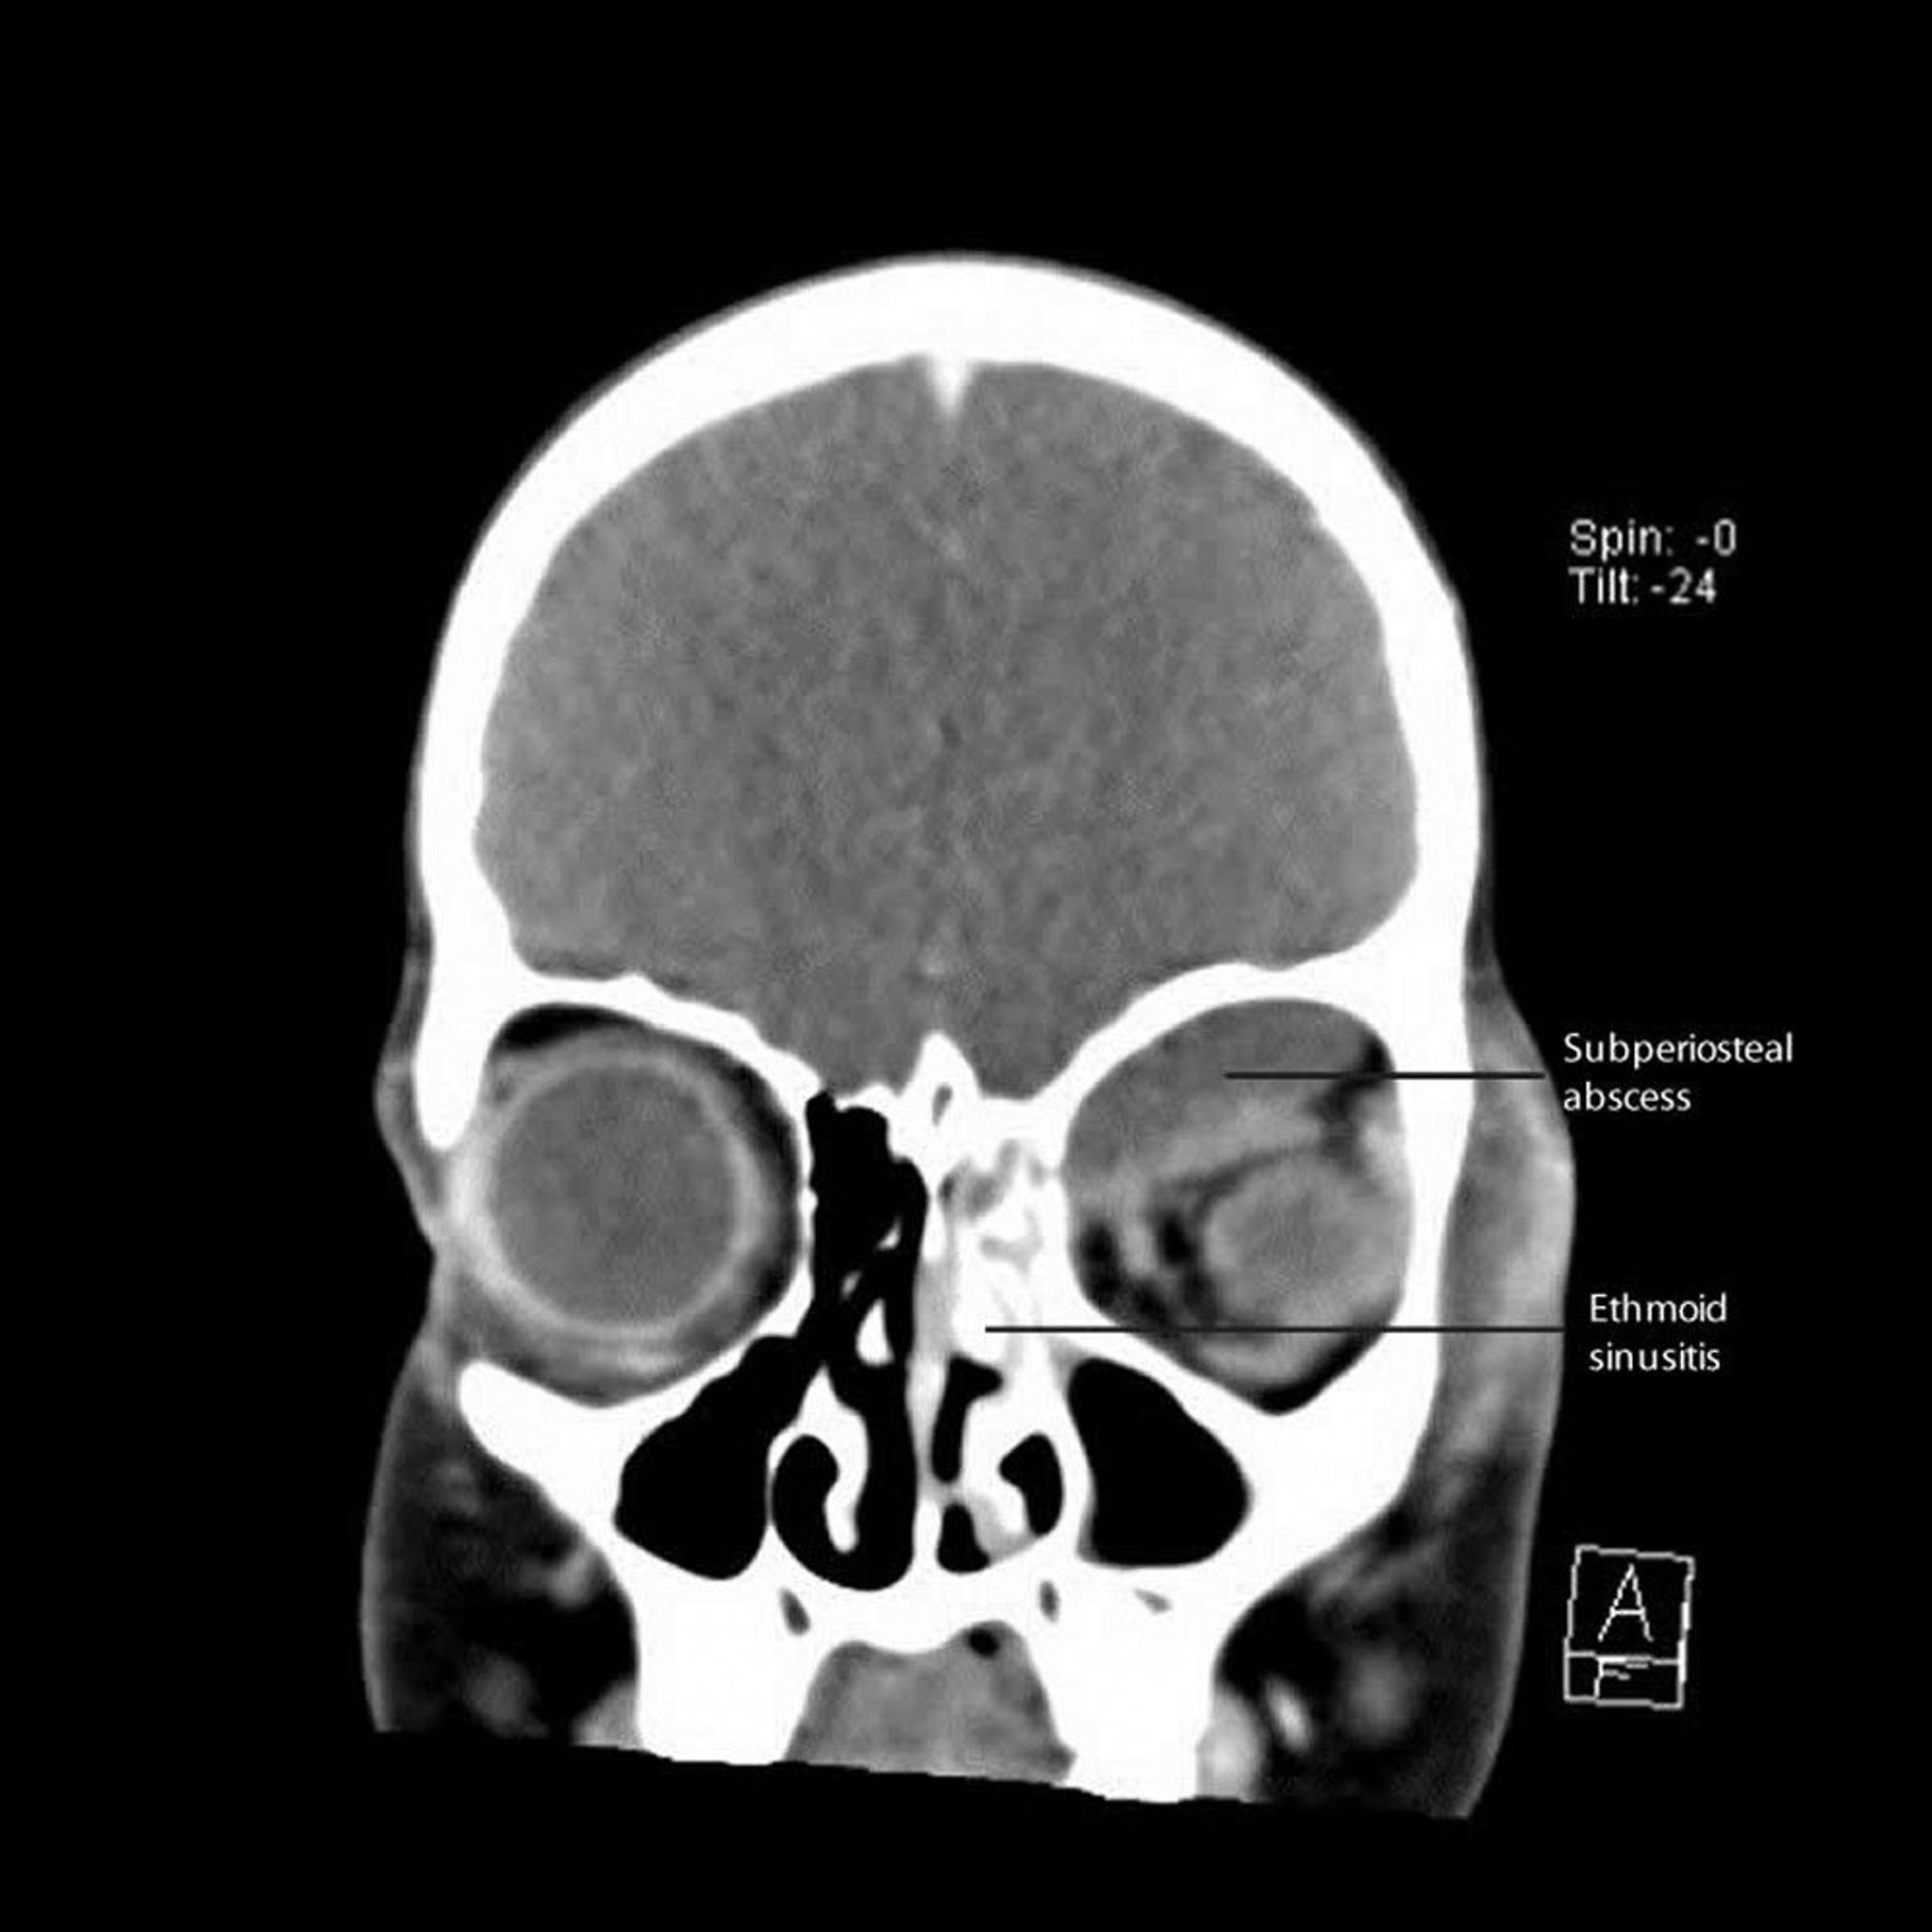

Ethmoid Sinusitis With Subperiosteal Abscess

This CT shows a left ethmoid sinusitis with adjacent subperiosteal abscess along the medial wall and roof of the orbit.

CT courtesy of James Garrity, MD.